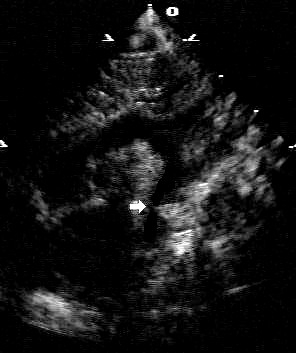

Two-dimensional suprasternal notch view of the aortic arch. Focal narrowing of the aortic arch (arrow) in the typical juxtaductal region

From the personal collection of Jeffrey Gossett, MD, Children's Memorial Hospital, Northwestern University, Chicago; used with permission